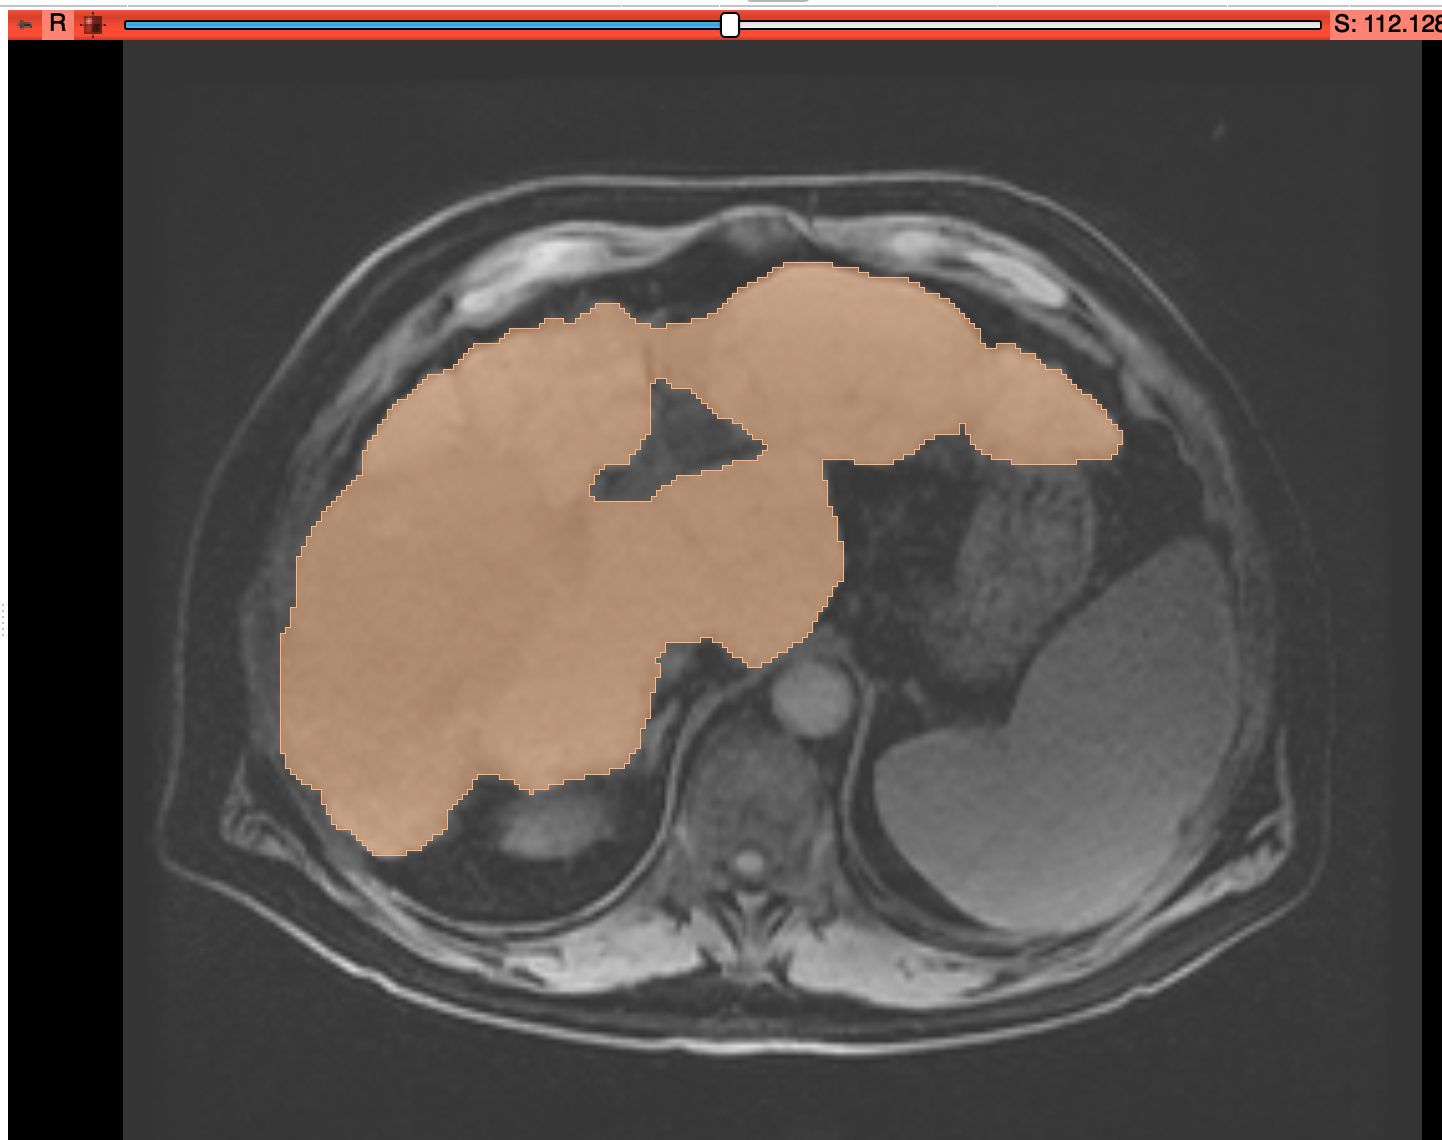

Fraunhofer MEVIS has recently released a standalone annotation tool called “MEVIS draw”: https://s.fhg.de/mevisdraw

MEVIS draw contains a version of the “CSI” tool (“contouring with snapping and interpolation”, while the snapping part is switched off in this application) that aims to provide an intuitive brush editor with nice interpolation features. It also supports a variety of import / export formats.

Illustrations